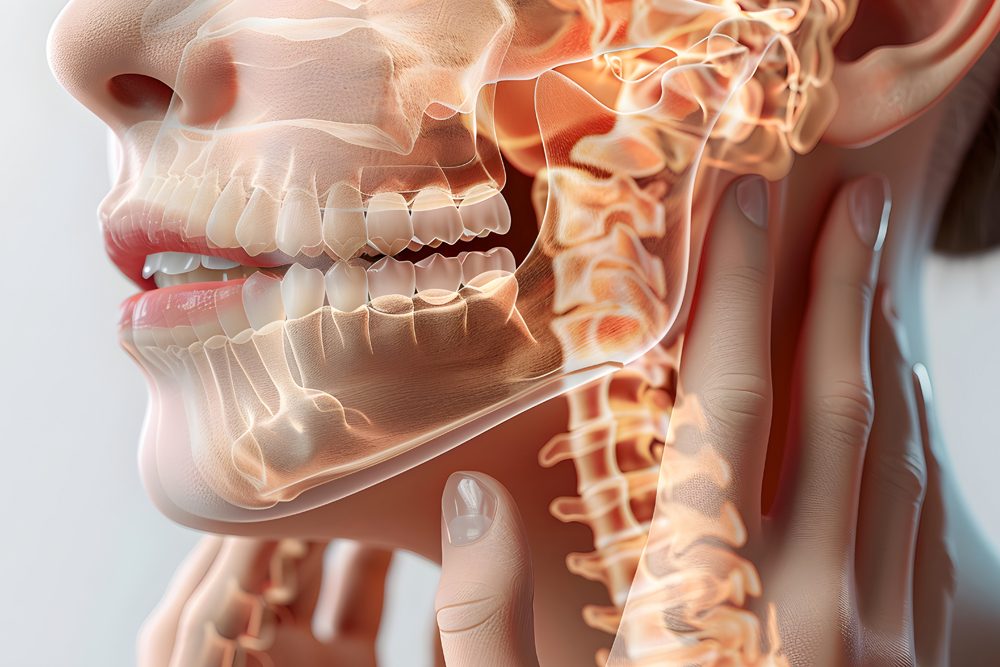

ATM y Bruxismo

ATM y Bruxismo

En Osteopatía Fisioterapia Taboada Sauvage, ofrecemos un enfoque integral y personalizado para tratar estos trastornos. Nuestro tratamiento de ATM y bruxismo se adapta a cada paciente, utilizando una combinación de técnicas que pueden incluir:

- Fisioterapia manual para aliviar la tensión muscular y mejorar la función de la mandíbula.

- Ejercicios terapéuticos para fortalecer y relajar los músculos de la mandíbula y el cuello.

- Técnicas de terapia miofascial y liberación muscular para reducir el dolor y mejorar el rango de movimiento.

- Reeducación postural para corregir las malas posturas que pueden contribuir al bruxismo o trastornos en la ATM.

- Uso de férulas o protectores dentales (si es necesario) para prevenir el daño a los dientes debido al bruxismo nocturno.

- Terapias de relajación y manejo del estrés, fundamentales si el bruxismo está relacionado con factores emocionales.

Beneficios del tratamiento de ATM y Bruxismo

Alivio del dolor mandibular y muscular

- Reducción de dolores de cabeza y migrañas

- Mejora de la movilidad mandibular y la función general de la ATM

- Prevención de desgaste dental causado por el bruxismo

- Relajación y reducción del estrés para evitar los episodios de rechinamiento dental

- Prevención de complicaciones a largo plazo, como el desgaste articular o el dolor crónico

¿Cómo es una sesión de tratamiento para ATM y Bruxismo?

Cada sesión de tratamiento en Osteopatía Fisioterapia Taboada Sauvage en Castelldefels está diseñada para adaptarse a las necesidades de cada paciente. Las sesiones suelen durar alrededor de 50 minutos y pueden incluir una combinación de técnicas manuales, ejercicios terapéuticos, y educación sobre hábitos y posturas correctas.

El tratamiento es intrabucal y se realiza de manera gradual, con el objetivo de lograr una mejora continua en la movilidad y funcionalidad de la ATM, así como en la reducción del dolor y los síntomas relacionados con el bruxismo.